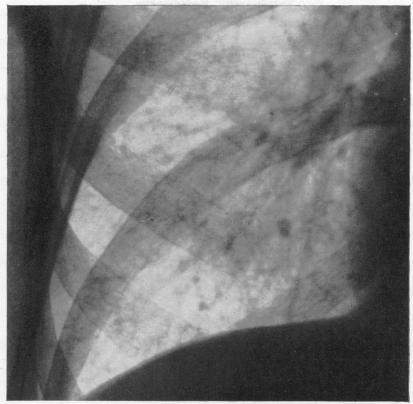

The incidence of siderosis in iron turners and grinders.

Br J Ind Med. 1946 Apr;3(2):78-82. doi: 10.1136/oem.3.2.78.